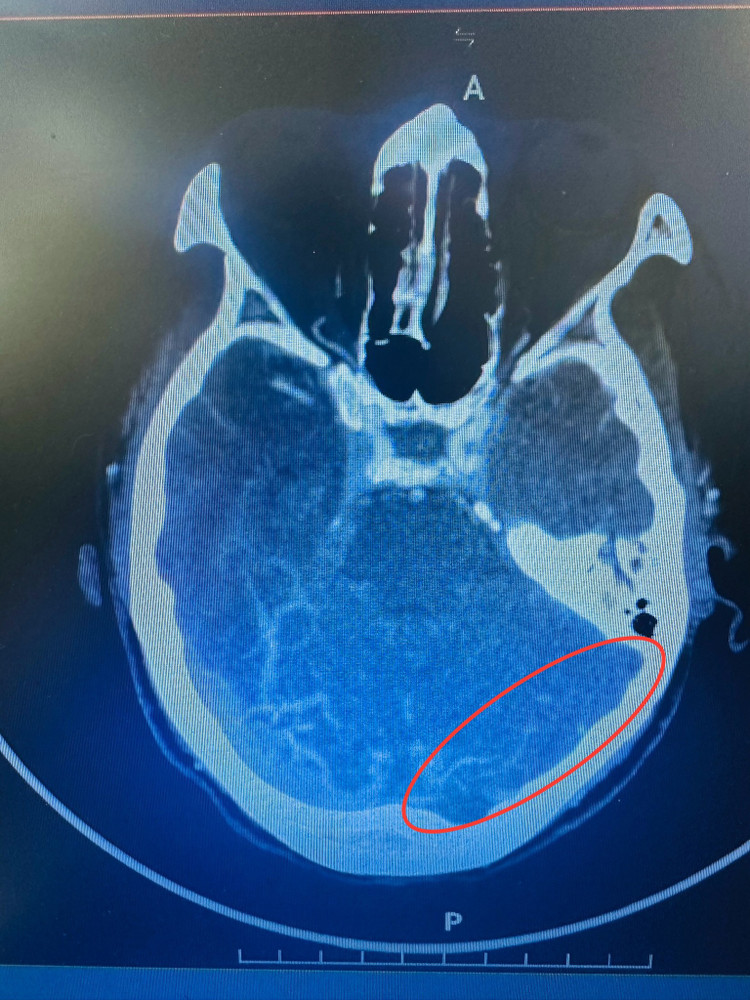

Bệnh nhân sau khi được chụp CLVT sọ não, dựng mạch máu não: Chẩn đoán xác định chảy máu não lớn chuyển dạng thùy đỉnh 2 bên do huyết khối xoang tĩnh mạch dọc trên và hội lưu xoang. Xét nghiệm D-Dimer tăng cao >5000 ng/mL.

![]() |

| Tổn thương não trên phim chụp - Ảnh BSCC |